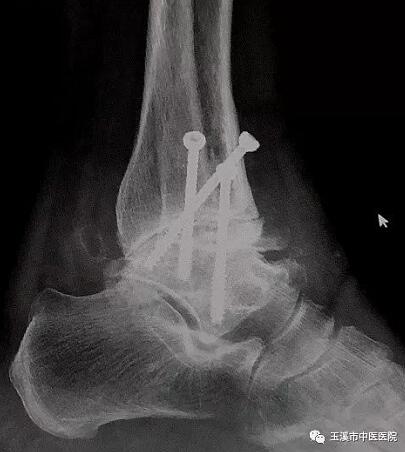

在醫(yī)務(wù)人員緊張的情況下,骨傷Ⅰ科克服種種困難,先后派出3名一線醫(yī)務(wù)人員赴千里之外的德欽縣人民醫(yī)院進(jìn)行對口援助。朱金富醫(yī)生是今年8月份去到藏區(qū)的,一到那里便積極投入工作。一位五十六歲藏族阿媽來到醫(yī)院看病時(shí),左踝關(guān)節(jié)疼痛、畸形三十余年了。 朱醫(yī)生將她收治入院,在相關(guān)檢查后,為她做了左踝關(guān)節(jié)融合術(shù)。術(shù)后藏族阿媽左踝關(guān)節(jié)功能明顯改善,生活及勞動(dòng)能力有所恢復(fù),一家人皆大歡喜。

術(shù)后X光片(左踝關(guān)節(jié)正位)